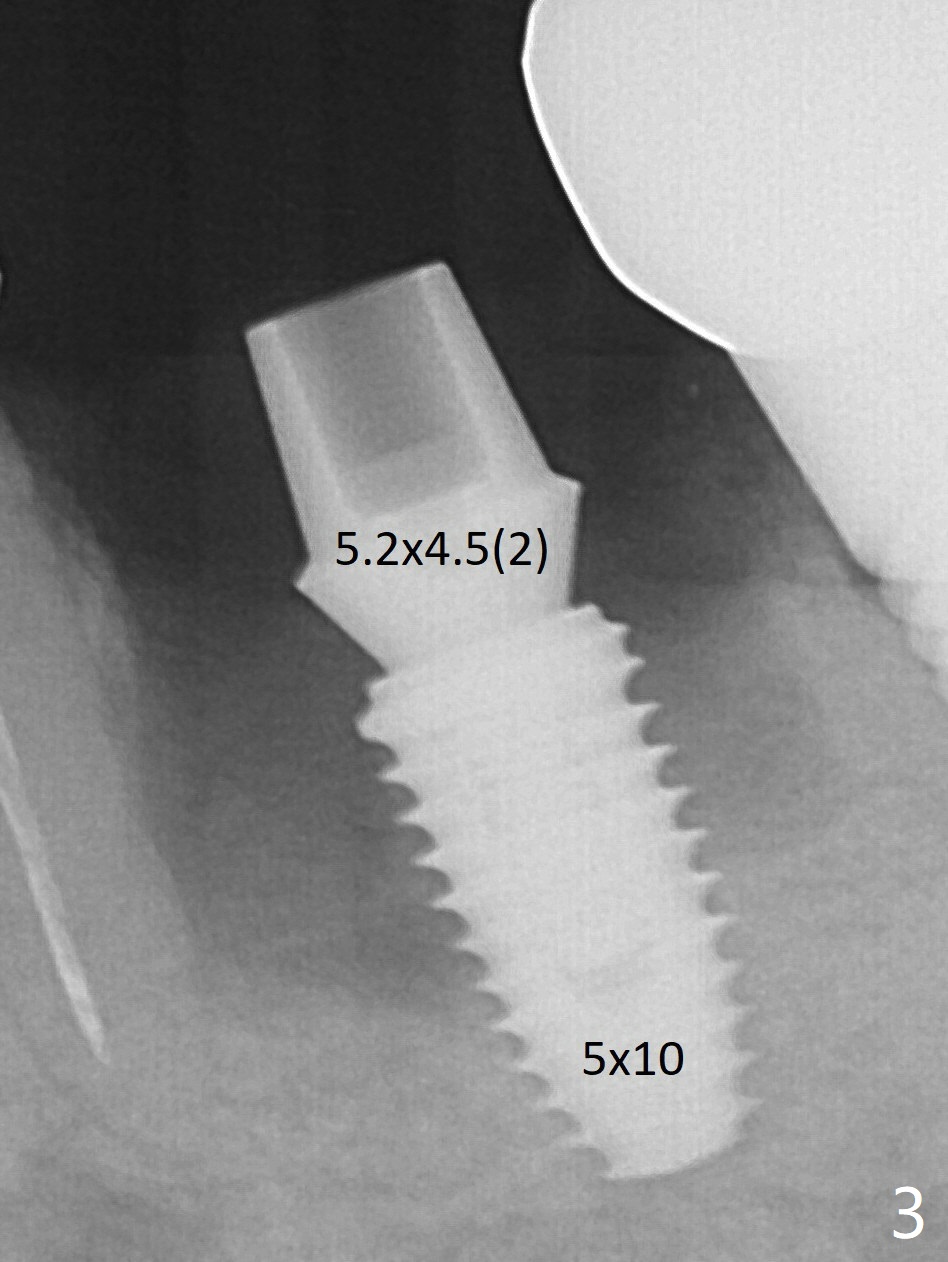

The hard bone contributes to primary stability of a 5x10 mm IS implant placed in the septum (Fig.3, 40 Ncm). A 5.2x4.5(2) mm cementation abutment seems to be short for immediate provisional. The final cementation abutment is expected to have 4 or 5 mm cuff (in fact 3mm). Note the large mesial and distal sockets, which will be filled by Vera Graft (allograft).